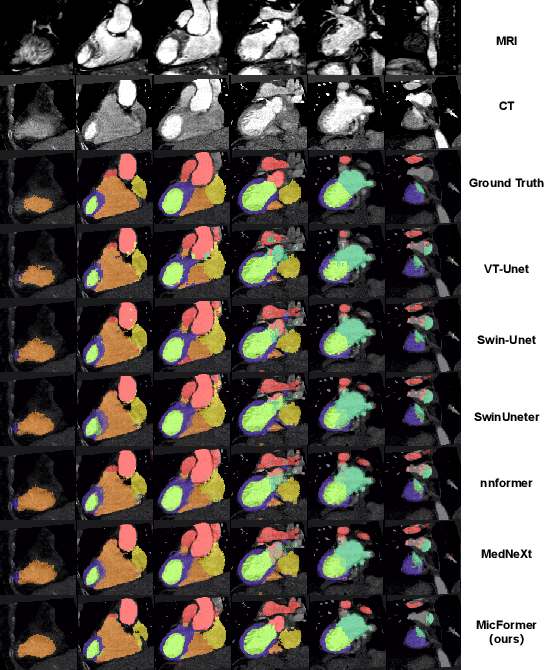

Abstract:The use of multimodal data in assisted diagnosis and segmentation has emerged as a prominent area of interest in current research. However, one of the primary challenges is how to effectively fuse multimodal features. Most of the current approaches focus on the integration of multimodal features while ignoring the correlation and consistency between different modal features, leading to the inclusion of potentially irrelevant information. To address this issue, we introduce an innovative Multimodal Information Cross Transformer (MicFormer), which employs a dual-stream architecture to simultaneously extract features from each modality. Leveraging the Cross Transformer, it queries features from one modality and retrieves corresponding responses from another, facilitating effective communication between bimodal features. Additionally, we incorporate a deformable Transformer architecture to expand the search space. We conducted experiments on the MM-WHS dataset, and in the CT-MRI multimodal image segmentation task, we successfully improved the whole-heart segmentation DICE score to 85.57 and MIoU to 75.51. Compared to other multimodal segmentation techniques, our method outperforms by margins of 2.83 and 4.23, respectively. This demonstrates the efficacy of MicFormer in integrating relevant information between different modalities in multimodal tasks. These findings hold significant implications for multimodal image tasks, and we believe that MicFormer possesses extensive potential for broader applications across various domains. Access to our method is available at https://github.com/fxxJuses/MICFormer